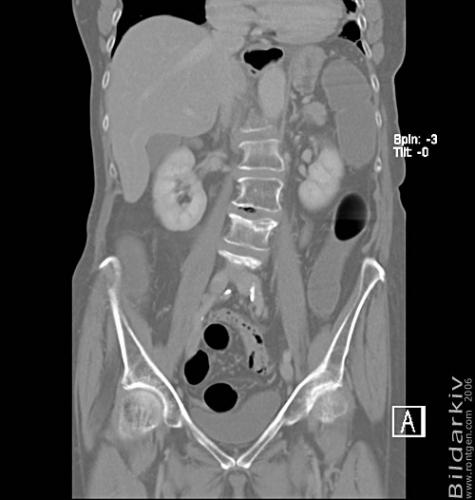

CT colon 28

Datortomografi av tjocktarmen (colon) med infunderad luft i tarmen samt med kontrast i blodbanan. Koronar bildserie.

CT multislice 16